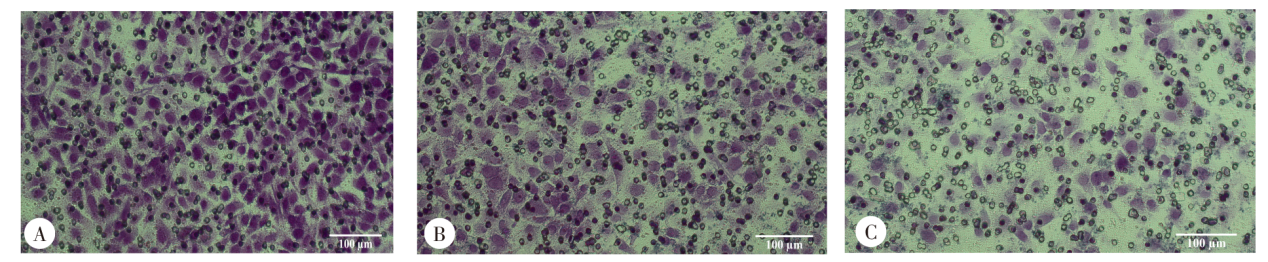

目的 探讨孕期刚地弓形虫感染后滋养层细胞表面白细胞免疫球蛋白样受体B4(LILRB4)的表达水平变化,以及对滋养层细胞功能及妊娠的影响。 方法 将人原代滋养层细胞培养于细胞培养皿中(1 × 107个/皿),分为对照组和感染组。感染组按细胞与弓形虫1:1感染,加入别藻蓝蛋白(APC)标记的抗人LILRB4单克隆抗体,固定破膜后加入别藻蓝蛋白偶联花青7染料(APC-Cy7)标记的抗人细胞角蛋白7(CK7)单克隆抗体和Alexa Fluor 488标记抗人波形蛋白单克隆抗体,流式细胞术检测LILRB4表达情况。取对数生长期的HTR-8/SVneo细胞接种于24孔板中(2 × 105个/孔),分为对照组和感染组。感染组按细胞与弓形虫1:1感染,加入鼠抗人LILRB4单克隆抗体(1:200)、Elab Fluor 647标记的羊抗鼠IgG抗体(1:200)孵育,封片后使用激光共聚焦显微镜拍照,Image J软件分析LILRB4蛋白表达的荧光强度。C57BL/6J野生型雌鼠40只与雄鼠20只、LILRB4-/-雌鼠40只与雄鼠20只分别按雌雄比2:1随机合笼过夜,次晨发现阴栓的雌鼠为孕0 d。野生型孕鼠随机分为野生型对照组和野生型感染组,LILRB4-/-孕鼠随机分为LILRB4-/-对照组和LILRB4-/-感染组,每组6只。孕8 d,野生型感染组和LILRB4-/-感染组孕鼠腹腔注射300个弓形虫速殖子,对照组注射等量生理盐水。孕14 d,解剖各组孕鼠子宫,观察胎盘、胎鼠发育情况。免疫组化检测野生型对照组和野生型感染组小鼠胎盘组织中LILRB4蛋白表达,Image J软件分析LILRB4蛋白阳性表达情况。蛋白质免疫印迹(Western blotting)检测野生型对照组和野生型感染组小鼠胎盘组织中LILRB4蛋白相对表达水平,以及野生型对照组、野生型感染组和LILRB4-/-感染组小鼠胎盘组织中白细胞介素-10(IL-10)和IL-12蛋白的相对表达水平。将HTR-8/SVneo细胞接种于细胞培养皿中(1 × 107个/皿),分为对照组、感染组和LILRB4阻断加感染组,LILRB4阻断加感染组加入LILRB4中和抗体预处理2 h,感染组和LILRB4阻断加感染组按细胞与弓形虫1:1感染,Western blotting检测3组HTR-8/SVneo细胞中IL-10和IL-12蛋白的相对表达水平。Transwell法检测弓形虫感染后HTR-8/SVneo细胞侵袭功能。所有数据均采用GraphPad Prism 9.0软件统计分析,两组比较采用独立样本t检验,多组比较采用单因素方差分析和Tukey事后检验。 结果 流式细胞术结果显示,对照组人原代滋养层细胞中LILRB4阳性细胞比例为(26.10 ± 1.99)%,高于感染组的(18.60 ± 1.13)%(t = 15.00,P < 0.01)。免疫荧光结果显示,感染组LILRB4蛋白的平均荧光强度为122.56 ± 5.24,弱于对照组的149.27 ± 3.50(t = 5.36,P < 0.05)。野生型对照组和LILRB4-/-对照组孕鼠毛发有光泽,精神正常,胎盘和胎鼠发育良好;野生型感染组和LILRB4-/-感染组孕鼠萎靡不振、毛发蓬松粗糙,胎盘缺血且胎鼠发育不良。野生型感染组胎盘和胎鼠体质量分别为(54.82 ± 7.12)和(140.59 ± 3.19)mg,低于野生型对照组的(72.51 ± 1.11)和(201.03 ± 17.37)mg(t = 4.25、5.92,P < 0.05、0.01);LILRB4-/-感染组胎盘和胎鼠体质量分别为(41.24 ± 2.80)和(68.25 ± 11.55)mg,均低于野生型感染组(t = 3.07、10.45,P < 0.05、0.01)。免疫组化结果显示,野生型对照组小鼠胎盘组织内高表达LILRB4蛋白,主要集中在细胞膜,野生型感染组LILRB4蛋白表达较少。野生型感染组LILRB4蛋白阳性表达率为(16.13 ± 2.55)%,低于野生型对照组的(36.64 ± 6.62)%(t = 5.00,P < 0.01)。Western blotting结果显示,野生型对照组小鼠胎盘内LILRB4蛋白相对表达水平为1.15 ± 0.05,高于野生型感染组的0.78 ± 0.10(t = 5.40,P < 0.05)。野生型感染组小鼠胎盘组织内IL-10蛋白相对表达水平为0.93 ± 0.09,低于野生型对照组的1.28 ± 0.16(Tukey事后检验,P < 0.05);LILRB4-/-感染组小鼠胎盘组织内IL-10蛋白相对表达水平为0.61 ± 0.10,低于野生型感染组(Tukey事后检验,P < 0.05)。野生型感染组小鼠胎盘组织内IL-12蛋白相对表达水平为1.08 ± 0.11,高于野生型对照组的0.55 ± 0.18(Tukey事后检验,P < 0.05);LILRB4-/-感染组小鼠胎盘内IL-12蛋白相对表达水平为1.67 ± 0.29,高于野生型感染组(Tukey事后检验,P < 0.05)。感染组HTR-8/SVneo细胞内IL-10蛋白相对表达水平为0.85 ± 0.05,低于对照组的1.15 ± 0.06(Tukey事后检验,P < 0.05);LILRB4阻断加感染组IL-10蛋白相对表达水平为0.72 ± 0.04,低于感染组(Tukey事后检验,P < 0.05)。感染组HTR-8/SVneo细胞内IL-12蛋白相对表达水平为0.89 ± 0.10,高于对照组的0.52 ± 0.14(Tukey事后检验,P < 0.05);LILRB4阻断加感染组IL-12蛋白相对表达水平为1.21 ± 0.04,高于感染组的0.89 ± 0.10(Tukey事后检验,P < 0.05)。感染组HTR-8/SVneo细胞侵袭细胞数为(178 ± 21)个,低于对照组的(278 ± 18)个(t = 45.60,P < 0.01),LILRB4阻断加感染组侵袭细胞数为(119 ± 9)个,较感染组侵袭细胞数量进一步减少(t = 5.50,P < 0.05)。 结论 弓形虫感染可致人滋养层细胞和小鼠胎盘组织LILRB4蛋白表达水平显著下调,LILRB4下调可促进IL-12表达,抑制IL-10产生,减弱滋养层细胞侵袭功能。

Objective To investigate the changes in the expression of leukocyte immunoglobulin-like receptor subfamily B member 4 (LILRB4) on the surface of trophoblast cells following Toxoplasma gondii infection during pregnancy, and to examine its effects on trophoblast cell functions and pregnancy outcomes. Methods Human primary trophoblast cells were incubated in cell culture dishes at a density of 1 × 10⁷ cells per dish and divided into control and infected groups. Cells in the infected group were infected with T. gondii at a ratio of 1:1, incubated with APC-conjugated anti-human LILRB4 monoclonal antibody, fixed, permeabilized, incubated with APC-Cy7-conjugated anti-human cytokeratin 7 (CK7) monoclonal antibody and Alexa Fluor 488-conjugated anti-human vimentin monoclonal antibody, and the expression of LILRB4 was detected by flow cytometry. HTR-8/SVneo cells in the logarithmic growth phase were seeded into 24-well plates at a density of 2 × 10⁵ cells per well and divided into control and infected groups. Cells in the infected group were infected with T. gondii at a ratio of 1:1, incubated with mouse anti-human LILRB4 monoclonal antibody (1:200 dilution) and Elab Fluor 647-conjugated goat anti-mouse IgG monoclonal antibody (1:200 dilution) and enveloped. Images were photographed with a confocal laser scanning microscope, and the immunofluorescence intensity of LILRB4 protein was analyzed using the Image J software. Forty female and 20 male wild-type mice of the C57BL/6J strain and 40 female and 20 male LILRB4-/- mice were randomly caged overnight, and presence of copulatory plugs in female mice on morning of the following day was considered gestational day 0. Wild-type pregnant mice were randomly assigned to wild-type control and infected groups, while LILRB4-/- pregnant mice were randomly divided into LILRB4-/- control and infected groups, with 6 mice in each group. Pregnant mice in wild-type and LILRB4-/- infected groups were intraperitoneally injected with 300 T. gondii tachyzoites on day 8 of gestation, while animals in the control groups received the same volume of physiological saline. On day 14 of gestation, all mice were sacrificed and their uteri were dissected to evaluate placental and fetal development. The expression of LILRB4 protein was detected using immunohistochemistry in mouse placental tissues in wild-type control and infected groups, and the percentage of positive LILRB4 protein expression was analyzed with the software Image J. The relative expression of LILRB4 protein was determined using Western blotting in mouse placental tissues in wild-type control and infected groups. Western blotting was used to detect the relative protein expression levels of interleukin-10 (IL-10) and IL-12 in mouse placental tissues of wild-type control group, wild-type infected group, and LILRB4-/- infected group. HTR-8/SVneo cells were seeded into cell culture dishes at a density of 1 × 10⁷ cells per dish and divided into control, infected, and LILRB4 blockade and infected group. Cells in the LILRB4 blockade and infected group were pretreated with LILRB4 neutralizing antibody for 2 hours, while cells in the infected and LILRB4 blockade and infected groups were infected with T. gondii at a ratio of 1:1. The relative expression of IL-10 and IL-12 proteins was quantified using Western blotting in HTR-8/SVneo cells in control, infected and LILRB4 blockade and infected groups. The invasive ability of HTR-8/SVneo cells was evaluated using Transwell assay following T. gondii infected. All statistical analyses were performed using the software GraphPad Prism 9.0. Difference of means between groups was tested for statistical significance with independent-sample t-test, and multiple-group comparisons were conducted with one-way analysis of variance (ANOVA) followed by Tukey’s post hoc test. Results Flow cytometry detected a higher percentage of LILRB4-positive human primary trophoblast cells in the control group than in the infected group [(26.10 ± 1.99)% vs. (18.60 ± 1.13)%; t = 15.00, P < 0.01], and immunofluorescence staining revealed that the mean fluorescence intensity of LILRB4 protein was lower in the infected group than in the control group [(122.56 ± 5.24) vs. (149.27 ± 3.50); t = 5.36, P < 0.05]. Pregnant mice in the wild-type and LILRB4-/- control groups presented shiny fur, normal mental state, and well placental and fetal development, while pregnant mice in the wild-type and LILRB4-/- infected groups exhibited remarkable low spirits, shaggy and rough fur, placental ischemia, and poor fetal growth. The mouse placental [(54.82 ± 7.12) mg vs. (72.51 ± 1.11) mg; t = 4.25, P < 0.05] and fetal weights [(140.59 ± 3.19) mg vs. (201.03 ± 17.37) mg; t = 5.92, P < 0.01] were lower in the wild-type infected group than in the wild-type control group, and the mouse placental [(41.24 ± 2.80) mg vs. (54.82 ± 7.12) mg; t = 3.07, P < 0.05] and fetal weights [(68.25 ± 11.55) mg vs. (140.59 ± 3.19) mg; t = 10.45, P < 0.01] were lower in the LILRB4-/- infected group than in the wild-type infected group. Immunohistochemical staining showed that the LILRB4 protein was highly positive in mouse placental tissues in the wild-type control group, with positive LILRB4 protein expression primarily found in cell membranes, and low LILRB4 protein expression was found in the wild-type infected group. The proportion of positive LILRB4 protein expression was lower in the wild-type infected group than in the wild-type control group [(16.13 ± 2.55)% vs. (36.64 ± 6.62)%; t = 5.00, P < 0.01]. Western blotting showed that the relative protein expression of LILRB4 in mouse placental tissues was higher in the wild-type control group than in the wild-type infected group [(1.15 ± 0.05) vs. (0.78 ± 0.10); t = 5.40, P < 0.05], and the relative IL-10 protein expression was lower in mouse placental tissues in the wild-type infected group than in the wild-type control group [(0.93 ± 0.09) vs. (1.28 ± 0.16); Tukey’s post hoc test, P < 0.05], and lower in the LILRB4-/- infected group than in the wild-type infected group [(0.61 ± 0.10) vs. (0.93 ± 0.09); Tukey’s post hoc test, P < 0.05]. The relative IL-12 protein expression was higher in mouse placental tissues in the wild-type infected group than in the wild-type control group [(1.08 ± 0.11) vs. (0.55 ± 0.18); Tukey’s post hoc test, P < 0.05], and higher relative IL-12 protein expression was detected in the LILRB4-/- infected group than in the wild-type infected group [(1.67 ± 0.29) vs. (1.08 ± 0.11); Tukey’s post hoc test, P < 0.05]. The relative IL-10 protein expression was lower in HTR-8/SVneo cells in the infected group than in the control group [(0.85 ± 0.05) vs. (1.15 ± 0.06); Tukey’s post hoc test, P < 0.05], and lower in the LILRB4 blockade and infected group (0.72 ± 0.04) than in the infected group (Tukey’s post hoc test, P < 0.05), and the relative IL-12 protein expression was higher in HTR-8/SVneo cells in the infected group than in the control group [(0.89 ± 0.10) vs. (0.52 ± 0.14); Tukey’s post hoc test, P < 0.05], and higher in the LILRB4 blockade and infected group than in the infected group [(1.21 ± 0.04) vs. (0.89 ± 0.10); Tukey’s post hoc test, P < 0.05]. In addition, the counts of invasive HTR-8/SVneo cells were lower in the infected group than in the control group [(178 ± 21) vs. (278 ± 18); t = 45.60, P < 0.01], and lower in the LILRB4 blockade and infected group (119 ± 9) than in the infected group (t = 5.50, P < 0.05). Conclusion T. gondii infection may significantly downregulate LILRB4 protein expression in human trophoblast cells and mouse placental tissues, and downregulation of LILRB4 promotes IL-12 expression and inhibits IL-10 production, thereby attenuating the invasive ability of trophoblast cells.